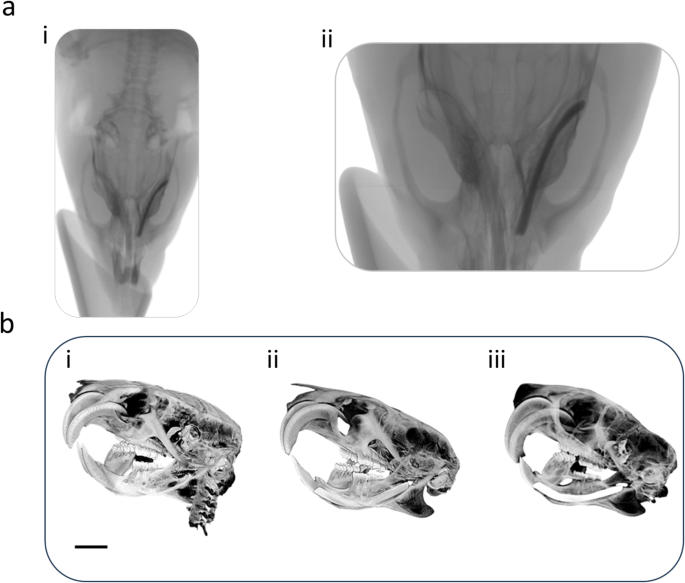

Radiological evaluation. (a)i-ii, Plain radiographs of dental implant after six weeks of dental implant surgery. (b) i Micro-CT images of rats with no dental implants., (b)ii, immediately after placing the implant, and (b) iii, after six weeks post-surgery. Distinct peri-implant radiolucency with no appreciable bone-to-implant contact is noted for both plain radiographs and micro-CT images. Image scale bar in (b) represents 10 mm.

All the animals survived the whole experimental time, and no operative or postoperative complications were encountered. The clinical and macroscopic evaluation revealed that all the prototypes for dental implants were well fixed in their respective dental sockets at the end of the trial period (Supplementary Video). All the rats presented healed peri-implant mucosa with no evidence of exudation, inflammation or crusting. Micro-CT investigation after 6 weeks post-implantation revealed distinct peri-implant radiolucency as a narrow radiolucent space in the range of 0.7–0.9 mm between the alveolar bone and the dental implant indicating absence of osseous/calcified characteristics in the integrating tissue (Fig. 3). Notably, absence of cervical lymphadenopathy throughout the investigation, along with the comparative histological evaluation (Supplementary Fig. 9). of the left submandibular lymph node, blood biochemistry, hemogram, cytokine levels, temperature, weight (Supplementary Tables 2–5) etc. indicated uneventful recovery.